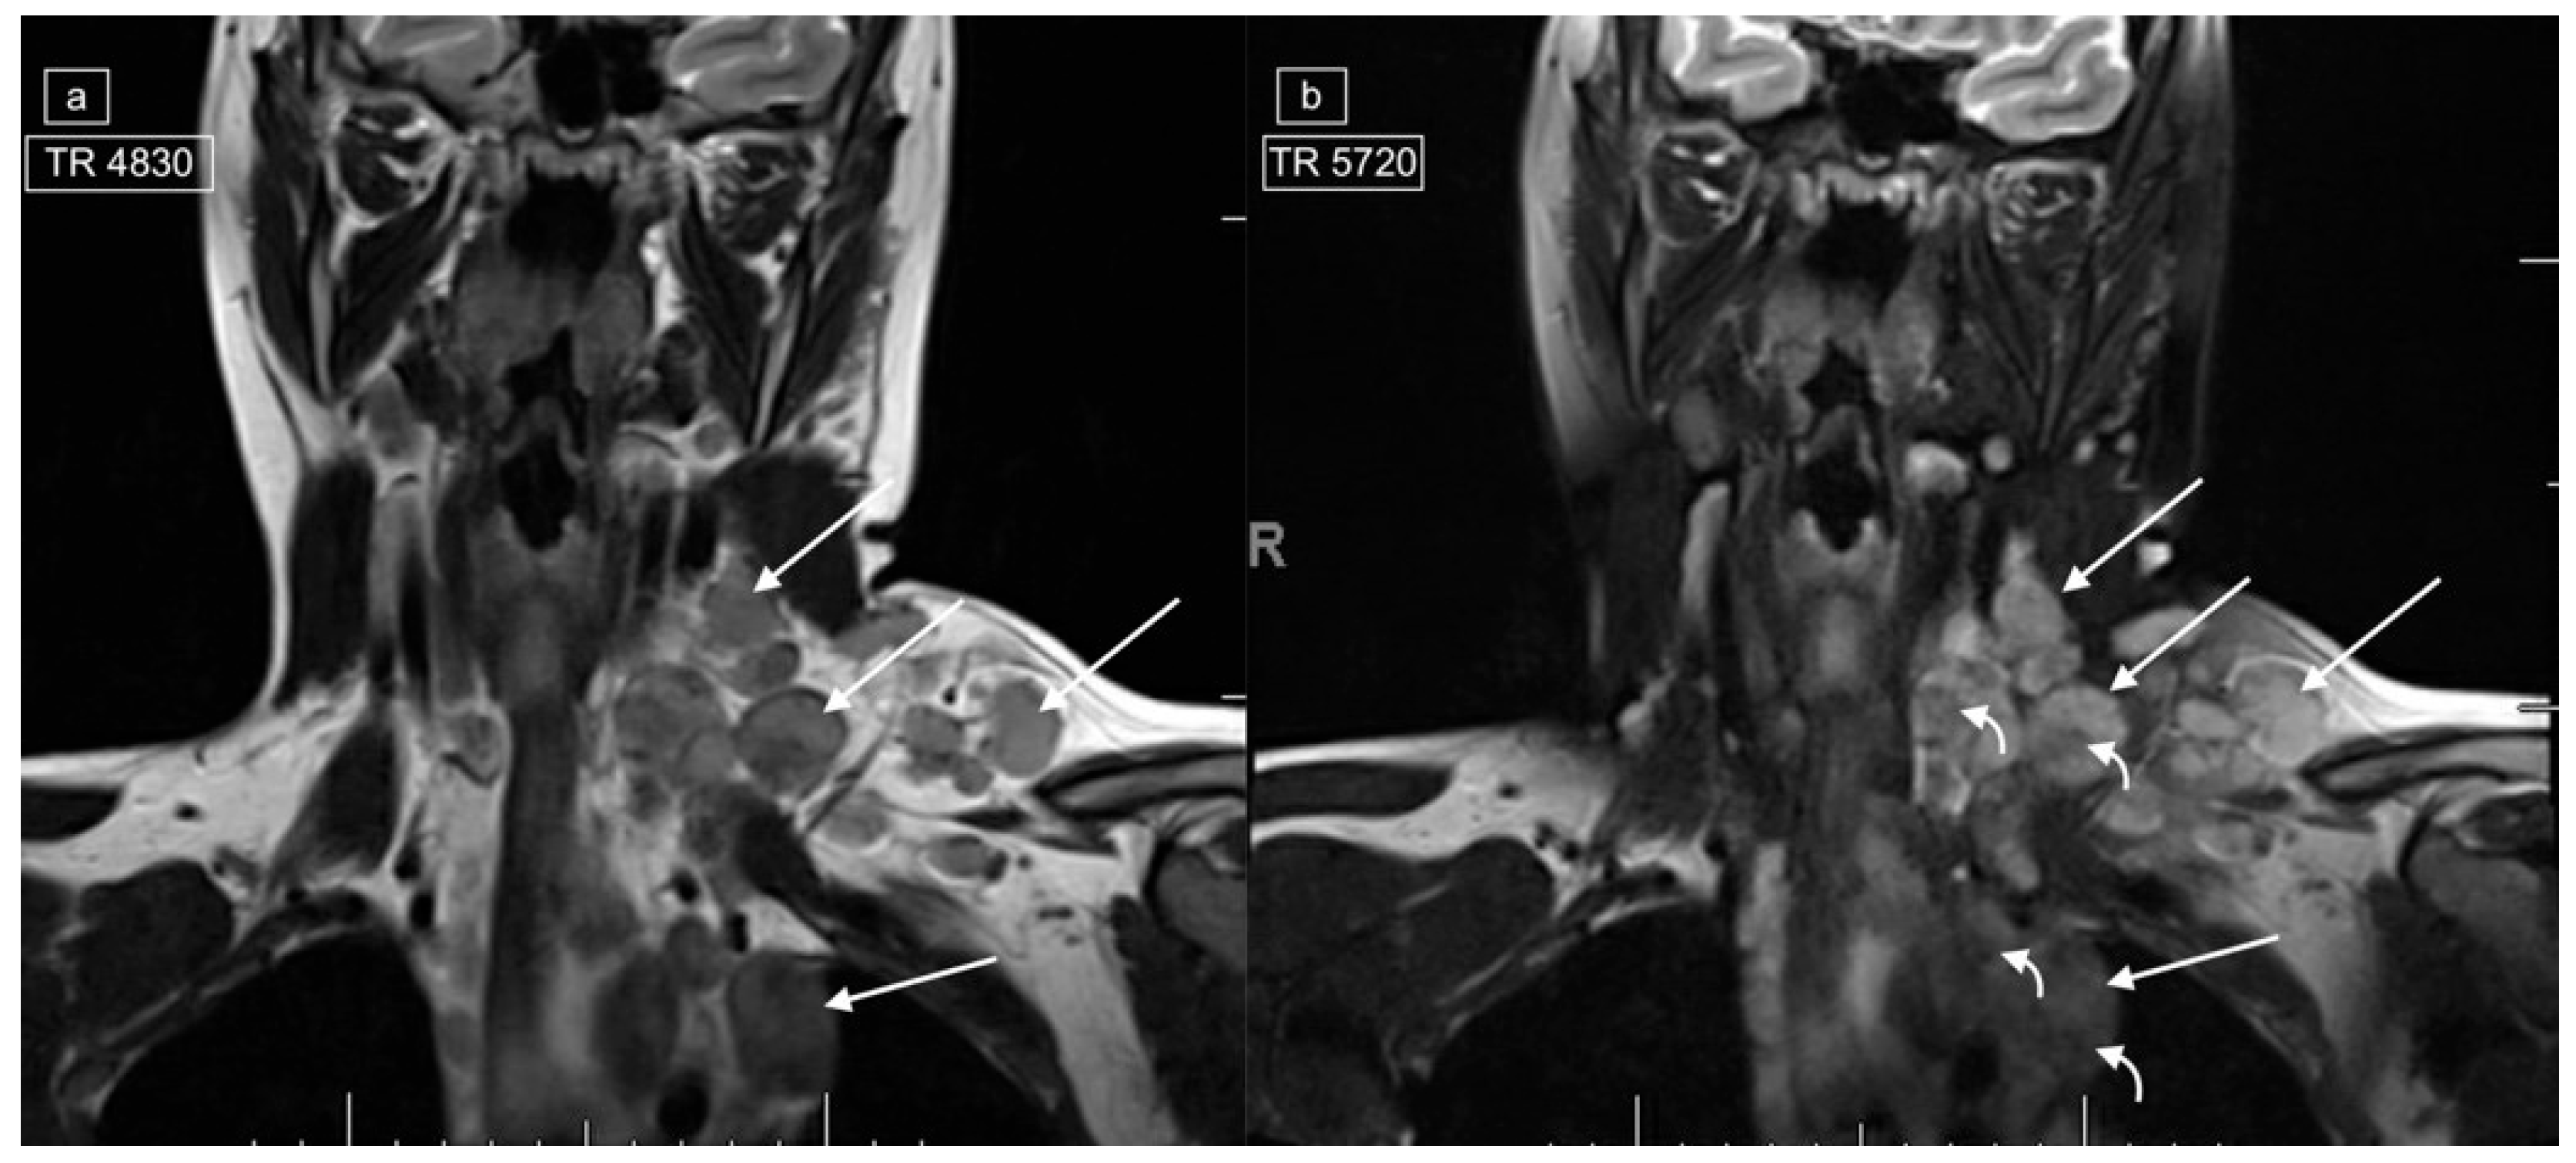

Figure 3.

Images demonstrating technical reasons for lower T2 signal of lymphadenopathy. MRI of the neck and superior mediastinum on coronal T2 with (a) a repetition time (TR) of 4830 and (b) a TR of 5720 [fat-suppressed sequence] in a 14-year-old male with a histologic diagnosis of nodular sclerosing Hodgkin lymphoma. The left cervical and mediastinal lymphadenopathy (straight arrows) show significantly lower signal with lower TR images (a), but even on the higher TR images, central foci within the pathological lymph nodes demonstrate low signal (curved arrows).